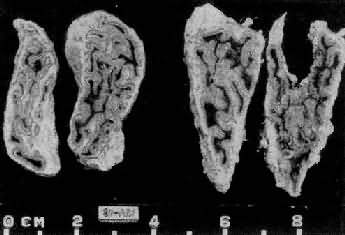

图15-13 肾上腺皮质弥漫增生(大体) 肾上腺肥大,皮质弥漫性增厚,切面呈脑回状

图15-14 肾上腺皮质弥漫增生 图15-13之镜下观,肾上腺皮质束状带弥漫性增厚 2.异位分泌ACTH或CRF肿瘤肾上腺变化与上述同。 3.肾上腺皮质结节性增生(adrenocortical nodular hyperplasia)其原因不明,有的呈家族性。双侧肾上腺明显肥大,重量可超过50g,在弥漫增生的基础上又有许多增生的结节,大小不等,直径从数毫米至2.5cm。镜下,弥漫增生者主为网状带及束状带细胞,而结节内多为束状带细胞,常见多量脂褐素,致结节呈棕褐色。患者血清ACTH水平下降。 4.功能性肾上腺肿瘤 除肿瘤变化外,血清中ACTH减少,致使肾上腺非肿瘤部分萎缩。 5.长期使用糖皮质激素类药物 例如地塞米松(dexamethasone),由于反馈抑制垂体前叶释放ACTH,故血清中ACTH等减少,双侧肾上腺皮质萎缩。 (二)醛固酮增多症 原发性醛固酮增多症(primary aldosteronism)是肾上腺皮质增生的细胞分泌过多的醛固酮所致,引起高血钠症、低血钾症及高血压。本症血清中肾素降低,这是由于钠潴留使血容量增多,抑制了肾素的释放。本病80%是由于功能性肾上腺肿瘤引起,其余为原因不明的两侧肾上腺皮质增生等,这种增生常呈弥漫性,有时也呈结节状,镜下主要为球状带细胞增生,有时也混杂些束状带细胞。 继发性醛固酮增多症是由于各种疾病造成肾素分泌增多所致,肾素可使血浆中的血管紧张素原转变为血管肾张素,后者刺激球状带细胞使醛固酮的分泌增多。